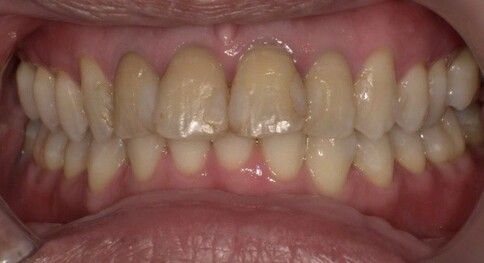

✨ 二、 兩顆的正中對決:對稱美學

Case 6:僅用兩顆全瓷冠解決色差與中軸偏差。